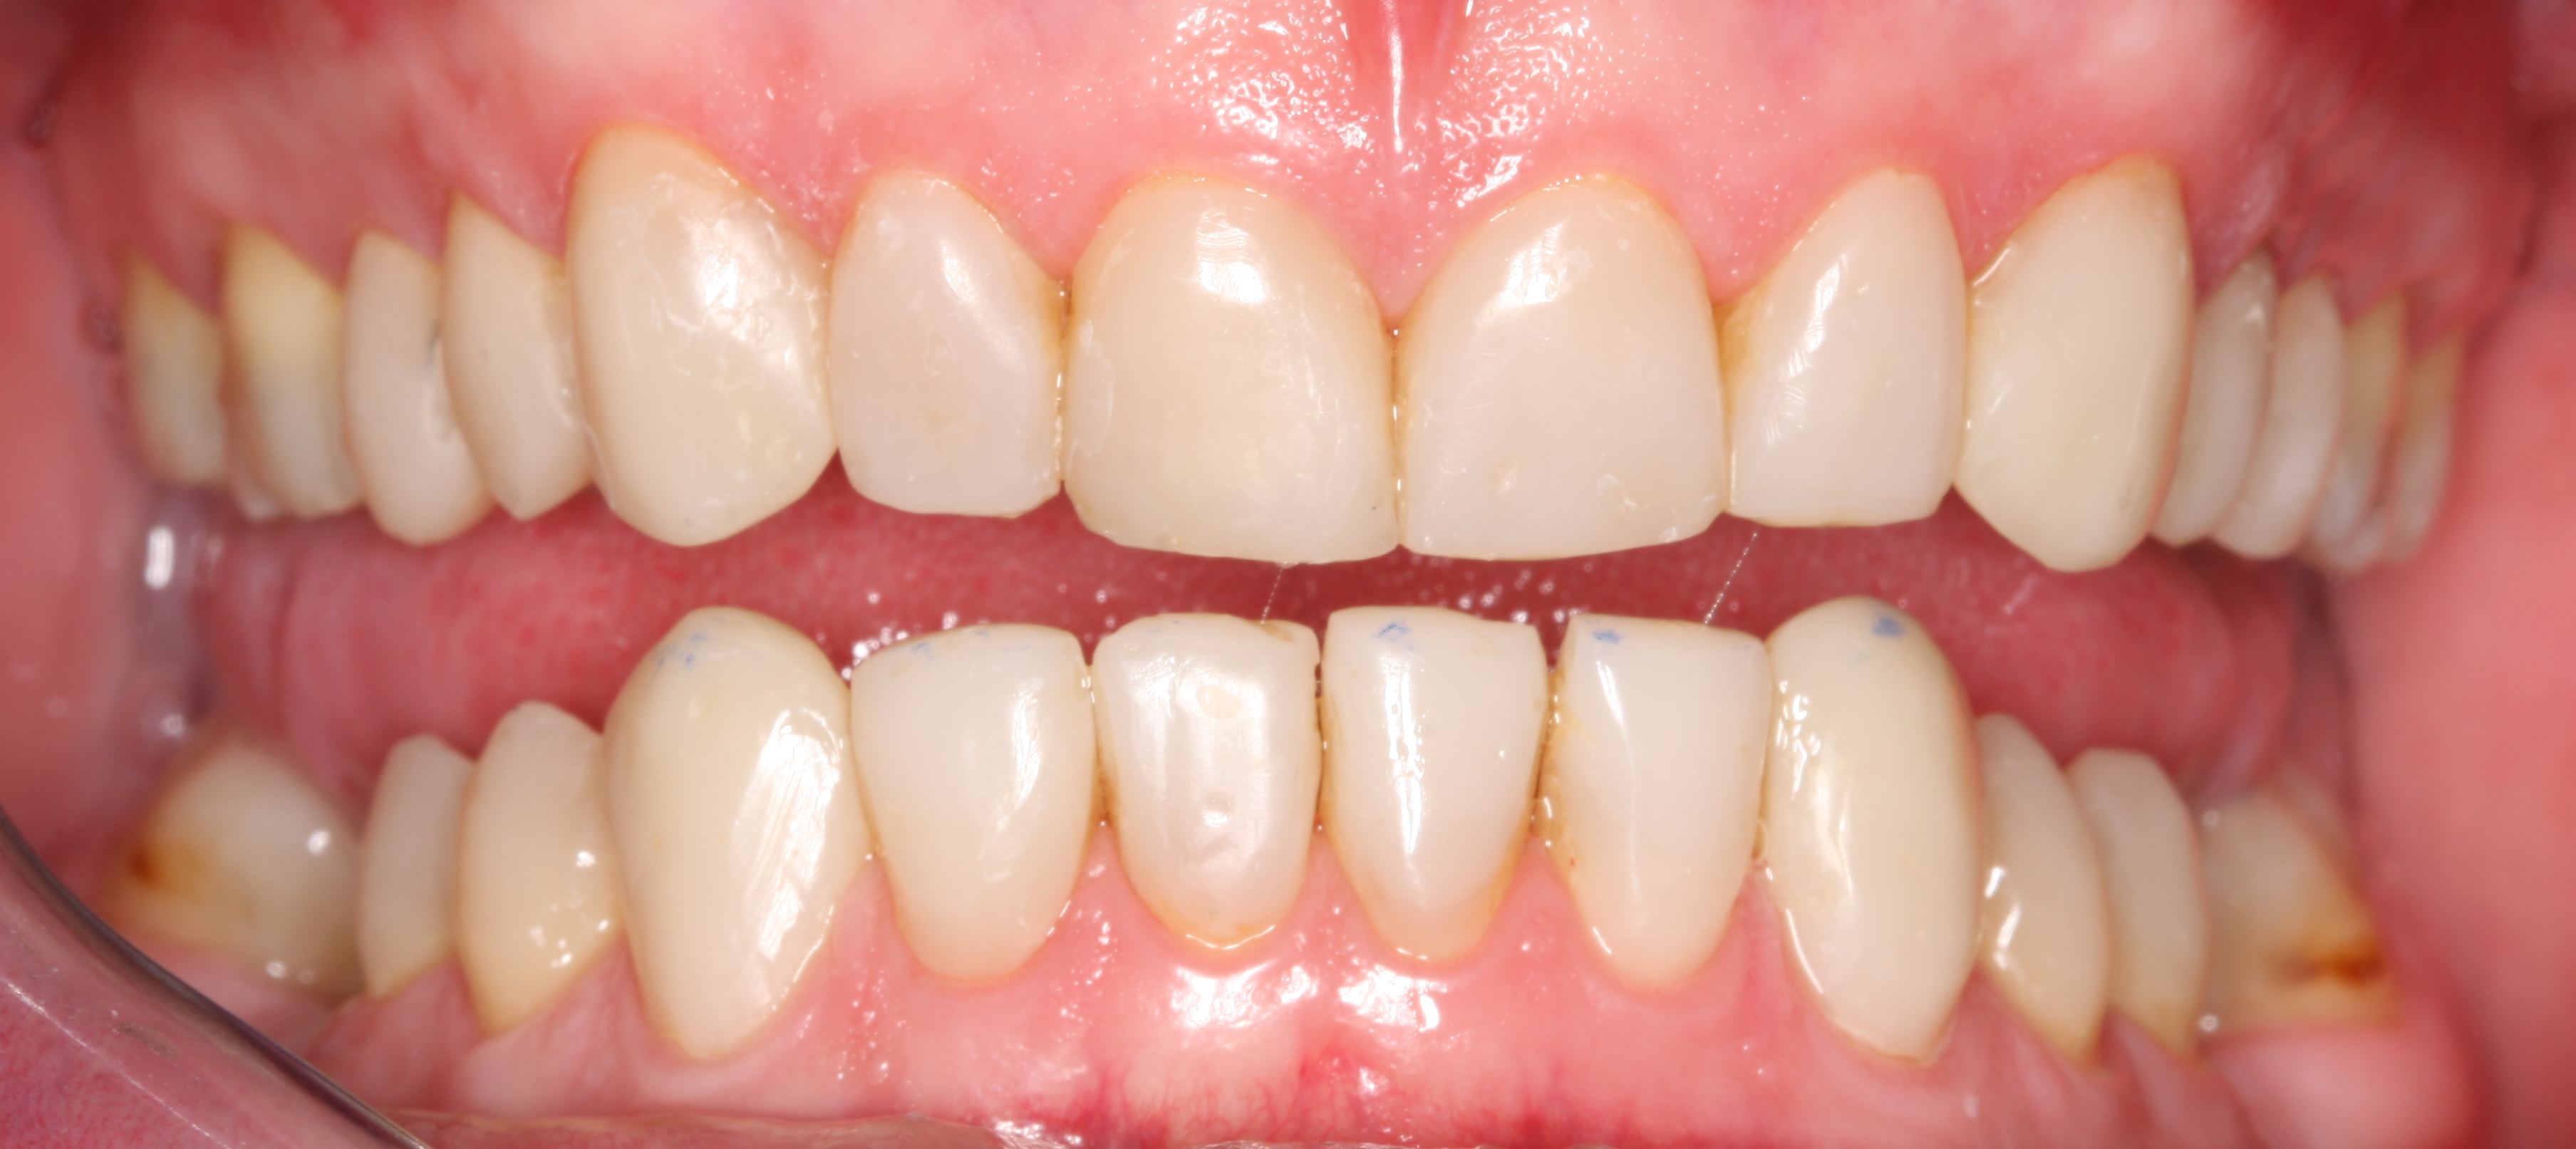

Dit zijn de voor en na fotos uit 2008:

In 2008 ben ik bij ACTA behandeld voor gebitsslijtage door bruxisme. De behandeling bestond toen uit het vervangen van alle vullingen, opbouw van kiezen, en het plaatsen van composiet facings op al mijn tanden. Ik was destijds zeer tevreden met het resultaat.